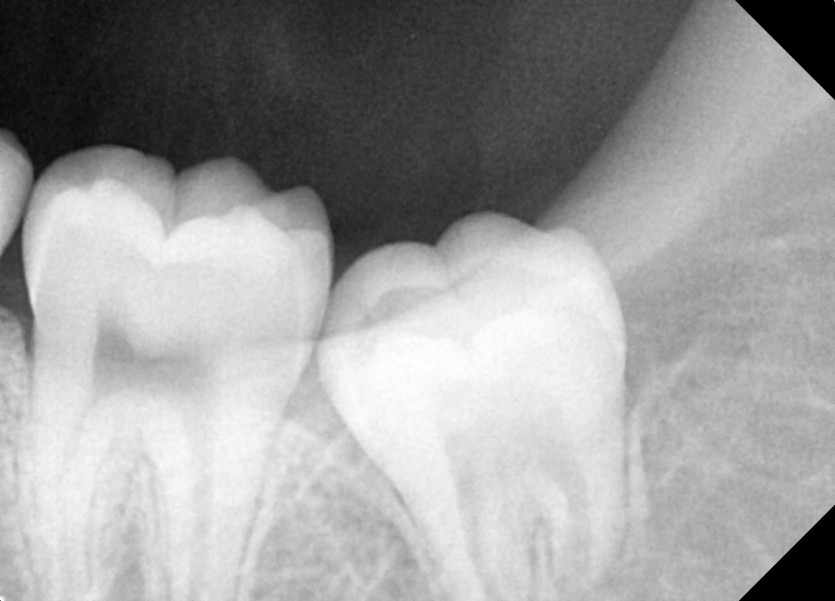

#18,28,38,48 사랑니 발치

구강 외과 전문의가 당일 발치했습니다.